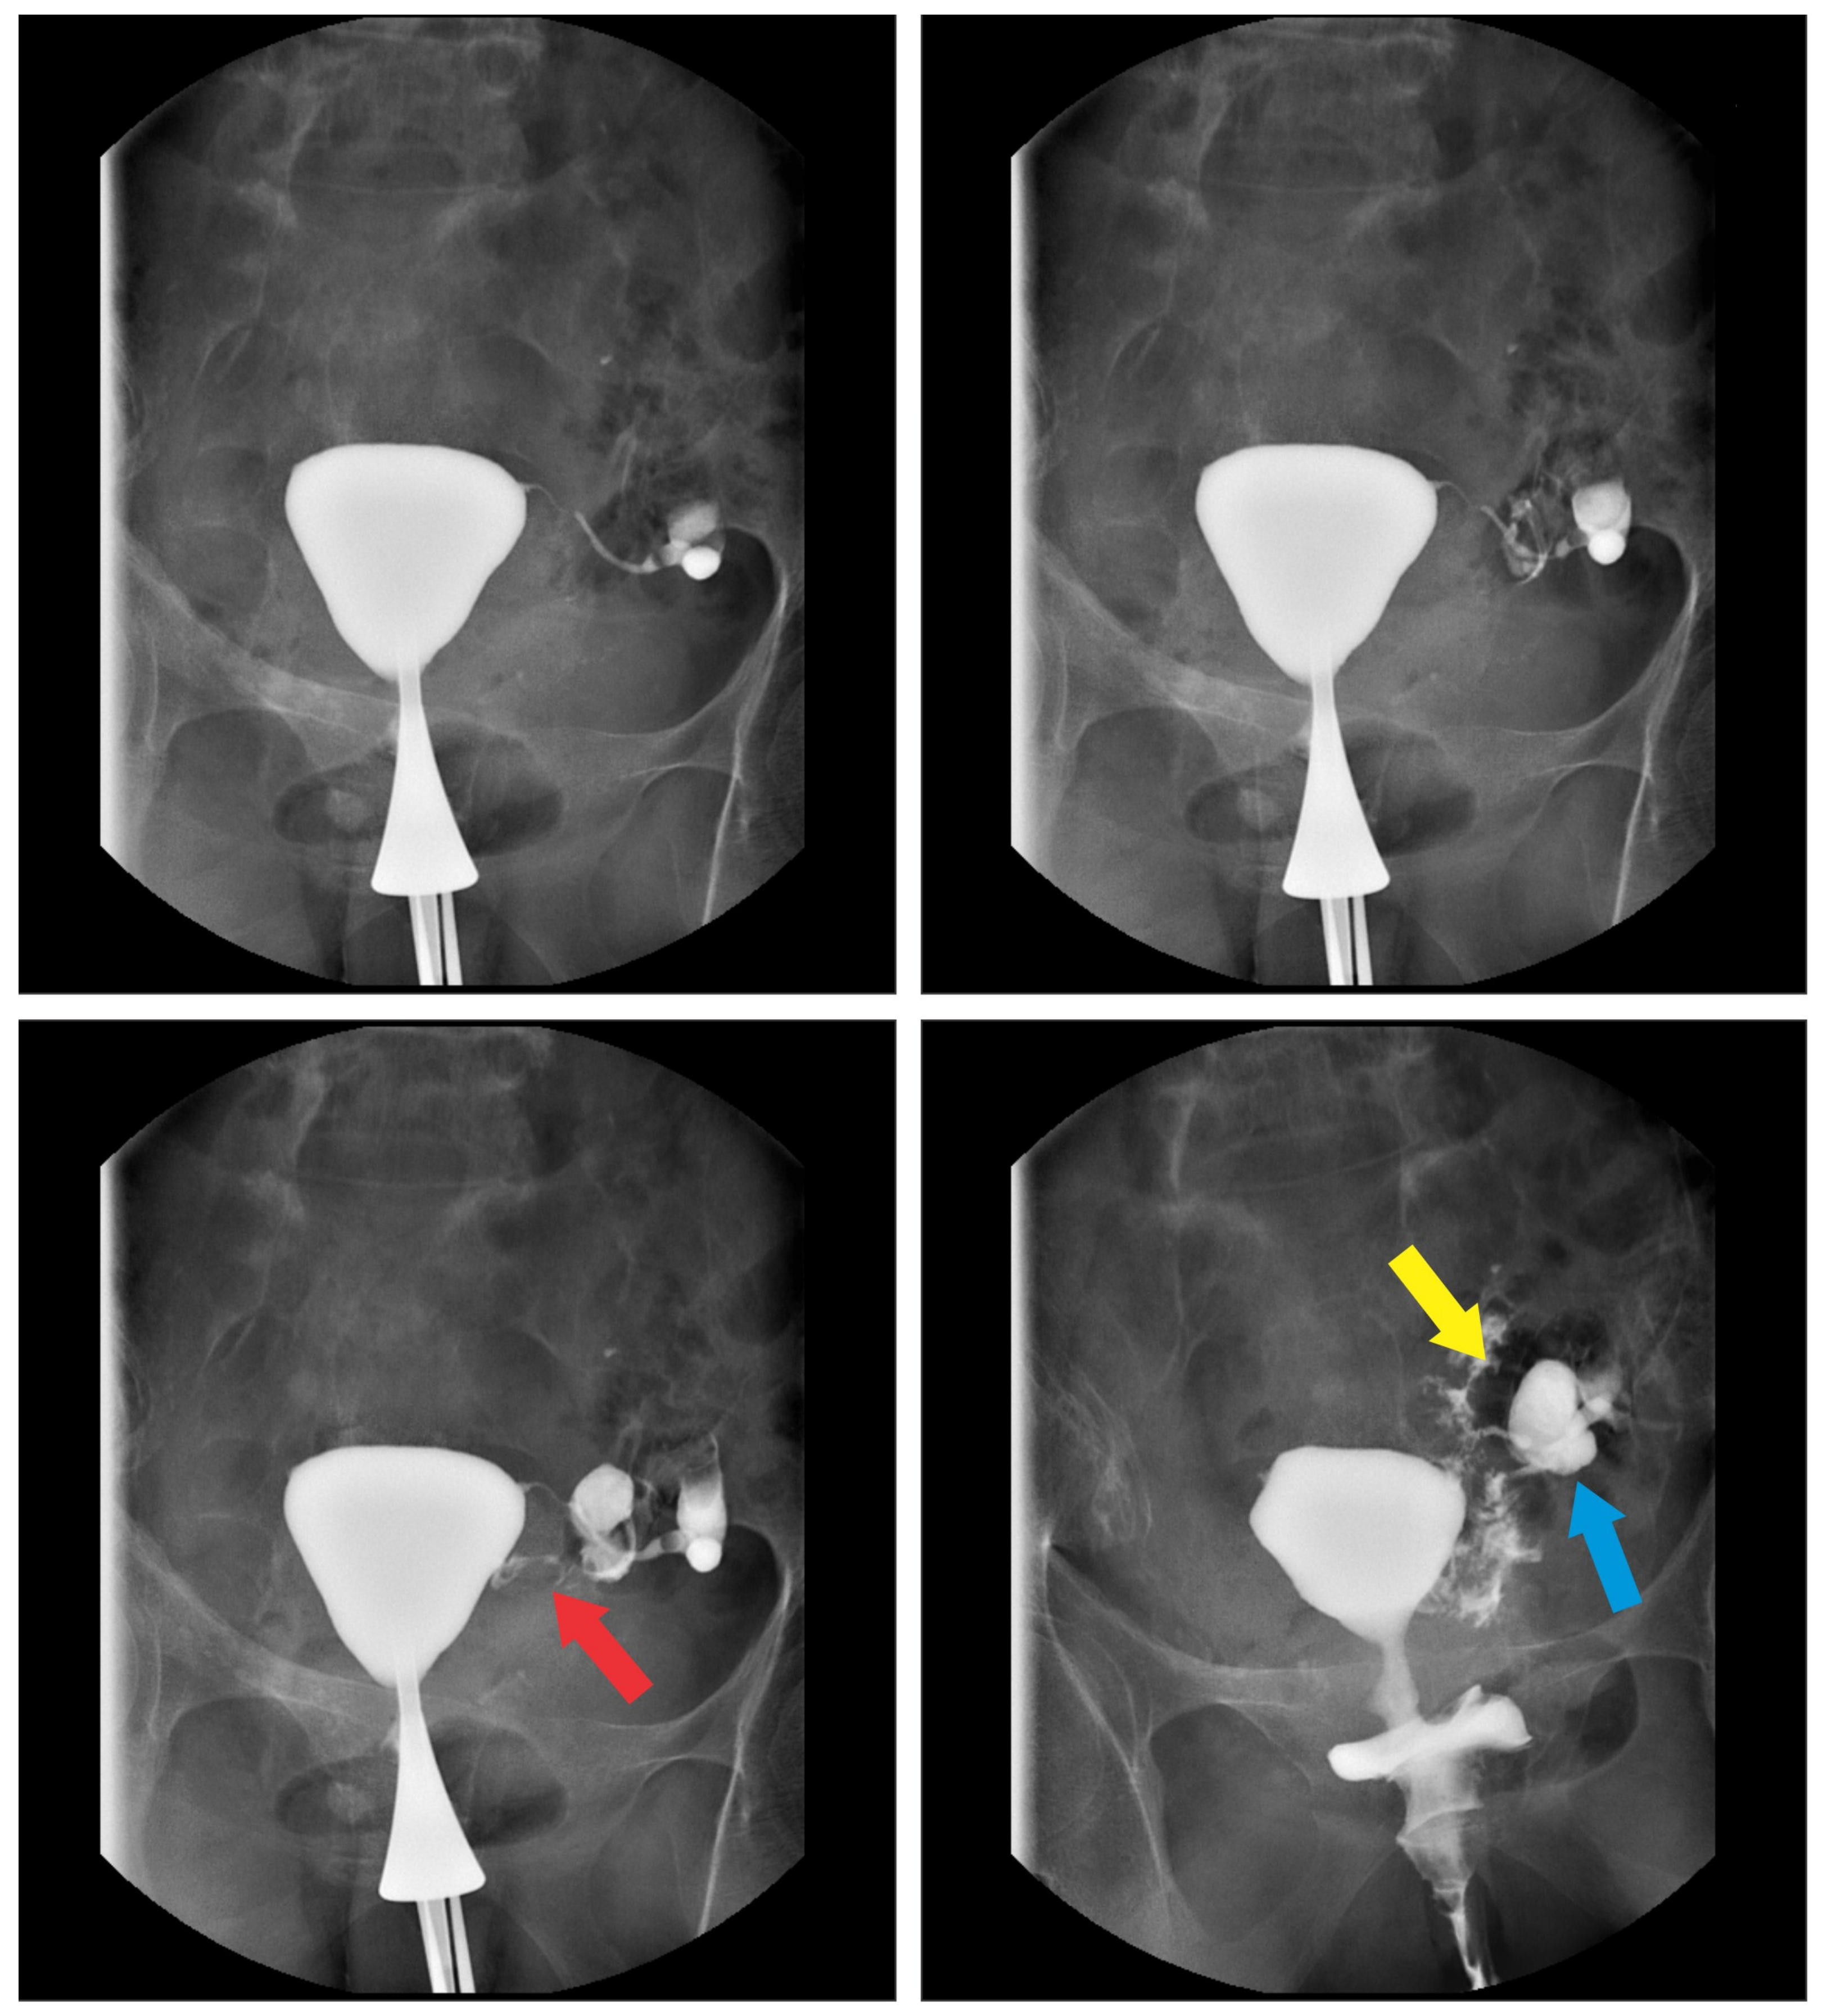

2. Case Report